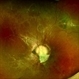

OPTOMAP - Description

- Fundus photograph of 43 year old male, hypertensive on medication, came for routine check up, and has been diagnosed to have poor vision left eye since childhood, denies any history of trauma. Vision left eye 6/18, Anterior segment normal, Fundus left eye shows excavated ,funnel-shaped optic nerve head, with central tuft of glial tissue obscuring the cup . The retinal vessels were seen emanating from the edge of disc in radial manner. In addition, the sectoral nasal retina shows localized area of hyperpigmented bony spicules like lesions. However, no history of nyctalopia or any other neurological disorder could be obtained.